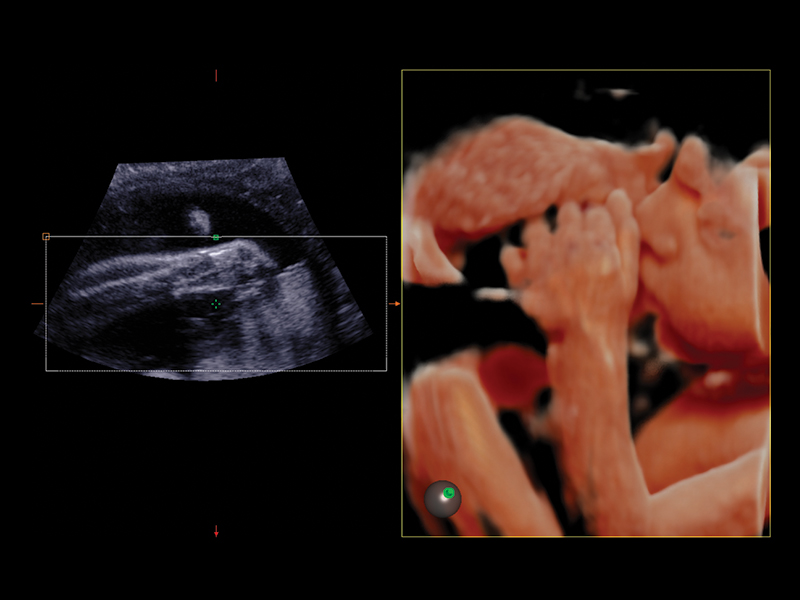

Realistic 3D/4D Depiction of the Fetus

Esaote attaches great value to the quality of its 3D/4D imaging in order to provide very detailed picture of the baby’s features, depending on the stage of fetal development. Its environment is provided by different modalities, based on how the volume can be processed and rendered.

Esaote XLight technology, with its realistic diffusion effects and shadows, emphasizes the anatomical details of the fetus in baby face scanning; XGlass creates a transparency effect; bone rendering is ideal to study the baby’s spine; TSI (Thick Slice Imaging) is suitable for well-defined and confined structures, such as the corpus callosum; finally, XSTIC accurately evaluates the fetal heart.

Clinical Images